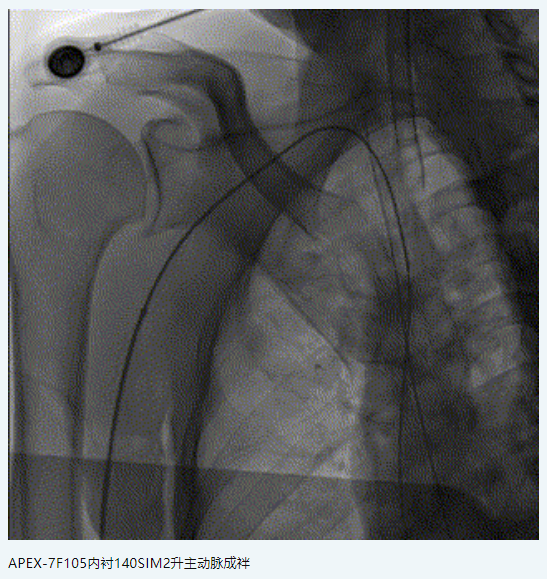

橈動脈系統(tǒng):APEX TRA SYSTEM 7F-105cm+140cm-SIM2

中間導管:中天中間導管 5F-125cm

4.頸內(nèi)動脈顱內(nèi)段迂曲,在此放置自膨閉環(huán)支架術后再狹窄發(fā)生率明顯比基底動脈和大腦中動脈升高,藥物洗脫球擴支架可能更適合這個部位的狹窄病變。

5.NOVA DES支架術后即刻血管成型效果好,術后再狹窄率低,但在曲度較大血管內(nèi)存在一定輸送難度,可采用“特洛伊木馬”技術,借助中間導管將支架輸送到位。

6.7F APEX TRA SYSTEM橈系統(tǒng):1、外徑細(2.32mm),對橈動脈侵擾小,內(nèi)腔大(0.081”):可兼容5F中間導管高到位;經(jīng)橈專用,弓部支撐性較長鞘、導引導管、中間導管、DA更強;APEX橈系統(tǒng)配套有130/140cm長SIM2,長SIM2管同軸治療可避免交換失敗,使顱內(nèi)病變更加便捷。